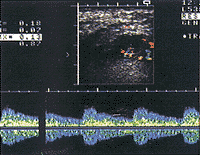

, 百拇医药 原发性舌癌的彩超显像特征 本组原发性舌癌瘤体彩色血流图显示率为87.1%。依彩色血流信号丰富程度可分为四型:1.无血供型;2.少血供型:病灶区周边无彩色血流信号,仅内部见星点状、短线状彩色血流信号(图4);3.富血供型:病灶区周边及内部均见线状、弧状彩色血流信号(图5);4.彩球型:病灶区几乎被丰富的彩色血流信号复盖,呈彩球状(图6)。频谱多普勒显示病灶区血流以动脉型为主,兼有少量静脉型频谱。4例彩色血流图显示阴性者,其中三例病灶小(T1期),另一例T2期为化疗后患者。T2期以上病例伴有患侧舌深动脉管径增大,血流速加大,搏动指数与阻力指数明显下降。

病灶内见点、线状彩色血流信号,频谱示动脉血供,RI为0.75

图4 左舌根鳞癌